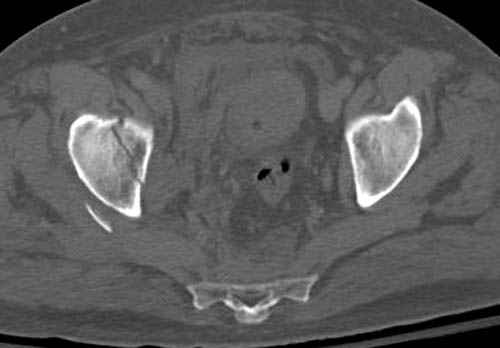

Дополнительно имеется перелом ацетабулума: задняя

колонна с полупоперечным переломом, и переломы костей лица.

На седьмой день зафиксирован перелом ацетабулума через задний доступ. Перед операцией для профилактики DVT, IVC фильтер, также получает Lovenox.

По снимку создается впечатление о высоком поперечном переломе, задней колонны, стенки; почему не пользовались *magic screw*?

Снимки здесь....